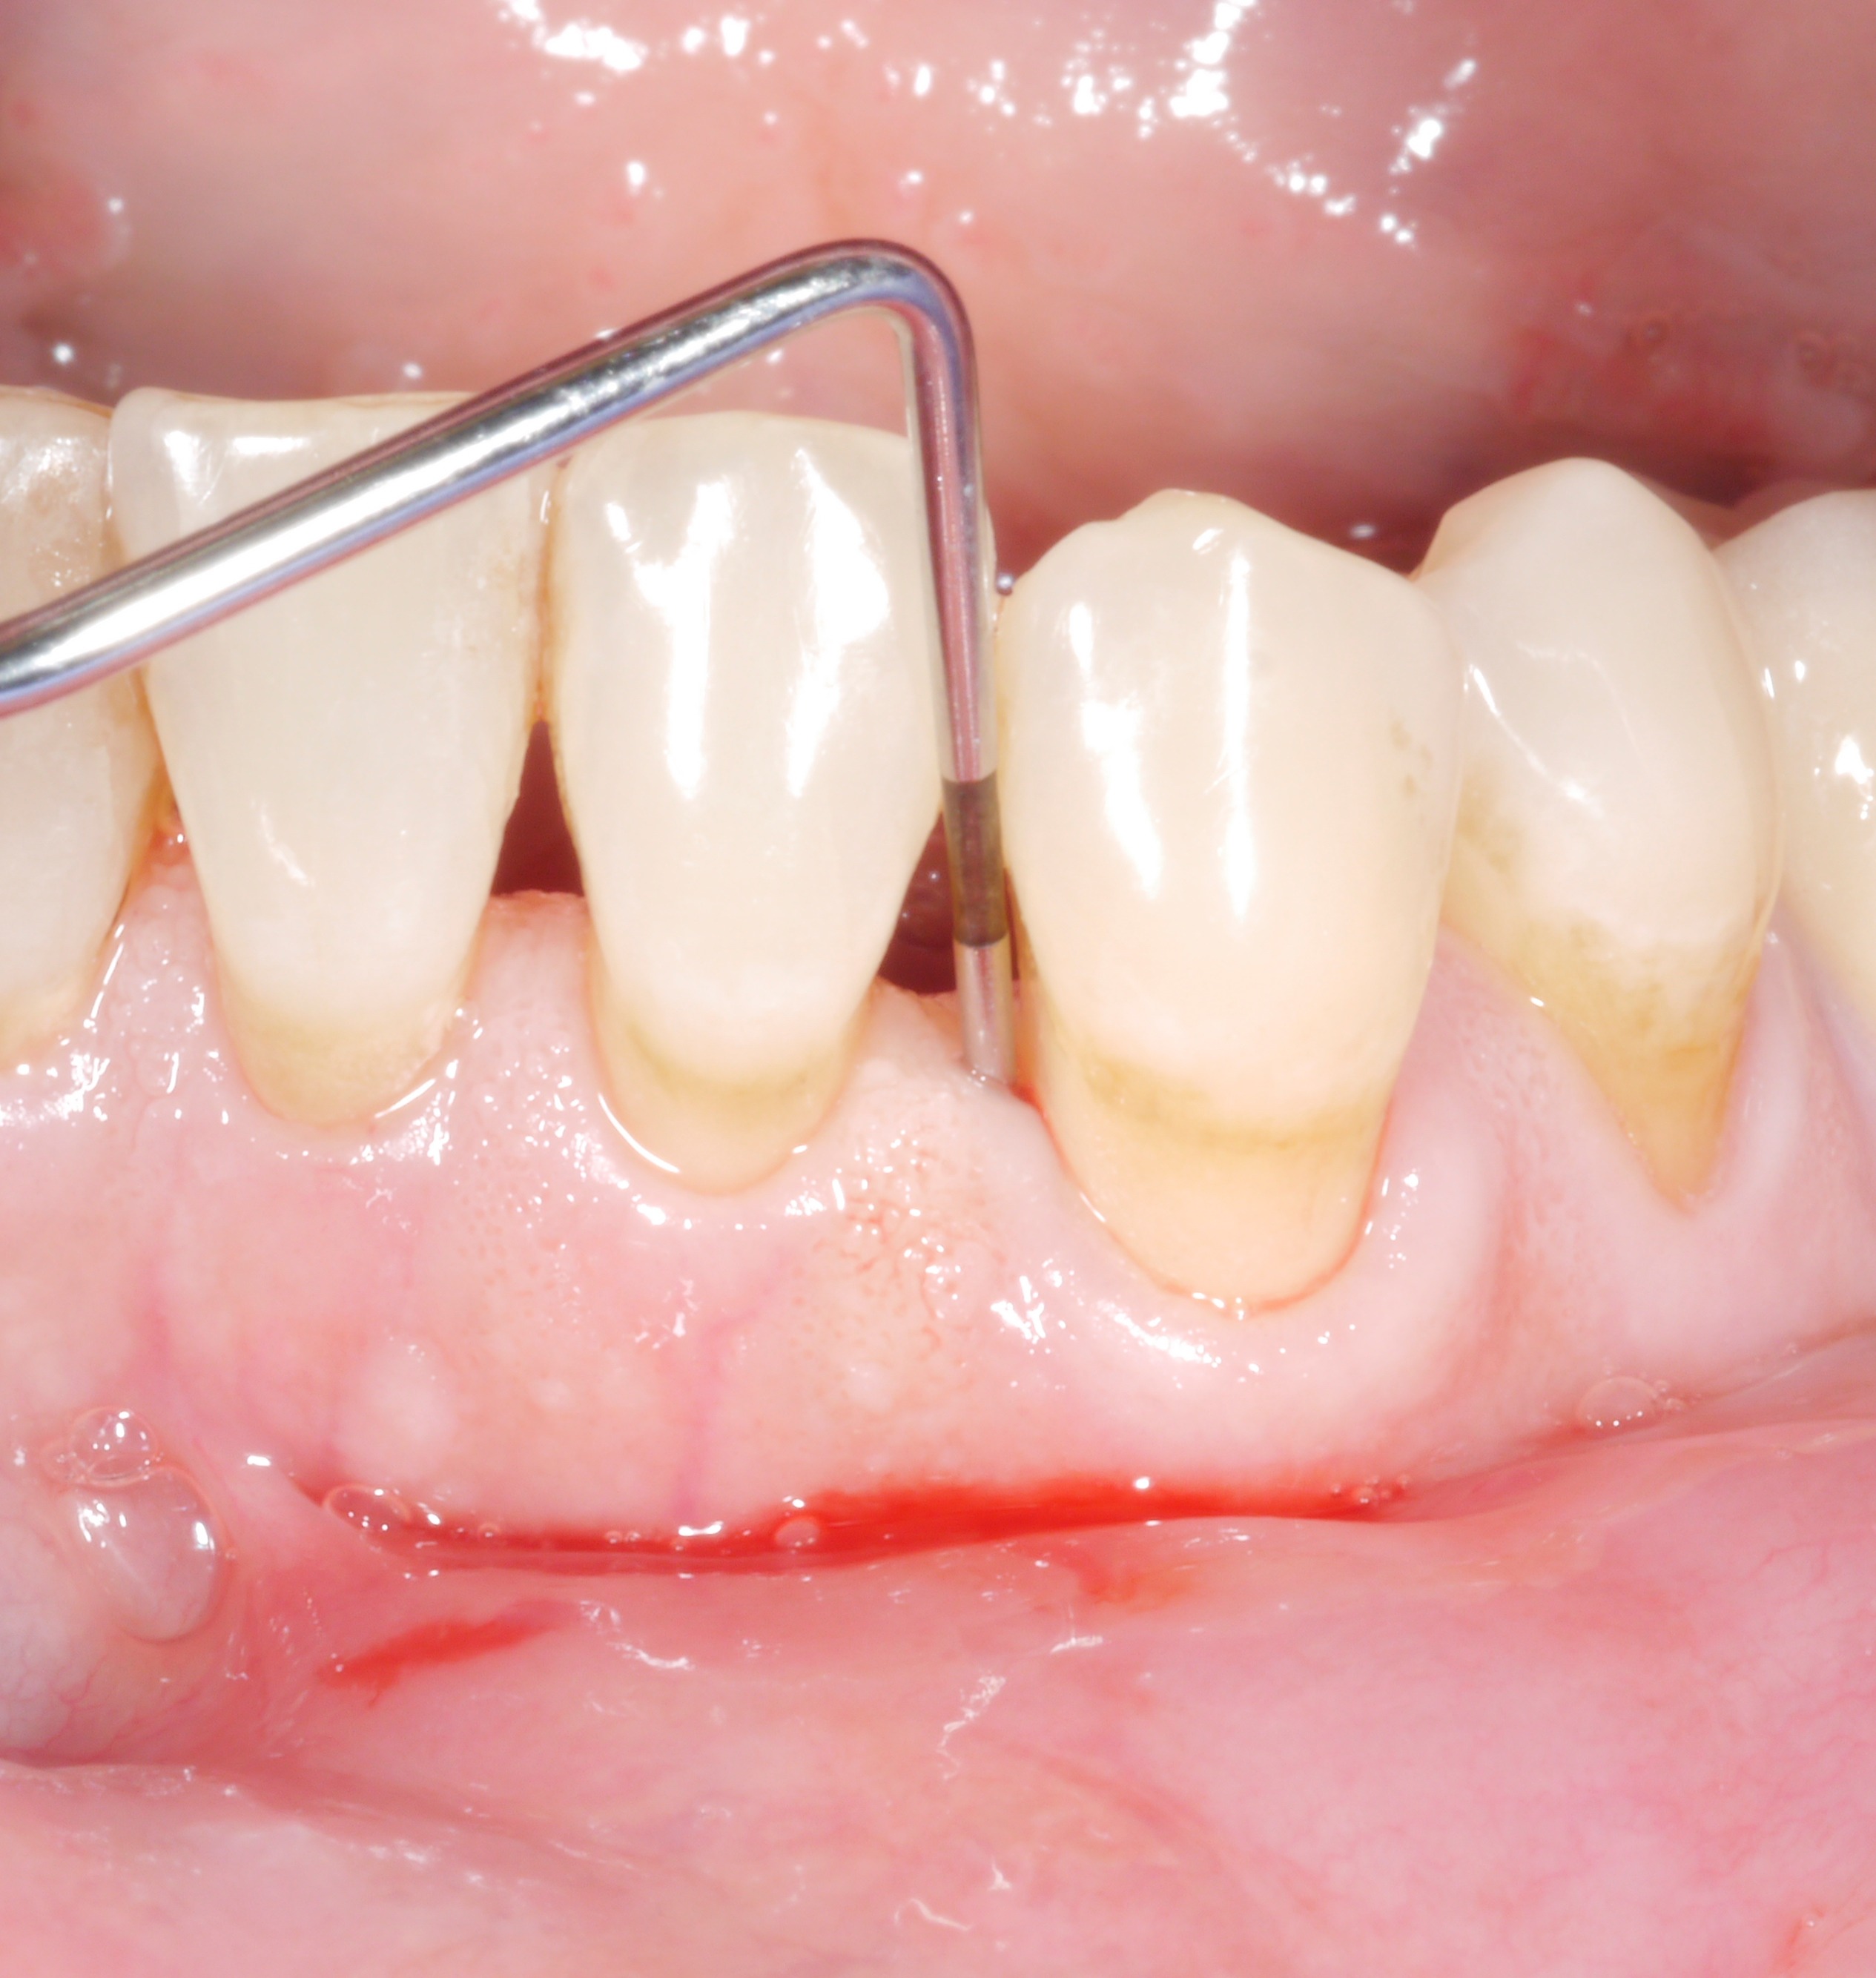

A residual pocket probing depth of 6 mm – is it a problem?

It is a situation we are all too familiar with: following the active phase of treatment, nearly all the patient’s teeth are now unaffected by increased pocket probing depths. However, there are still 1 or 2 places where the treatment goal has unfortunately not been achieved. The following thought might arise: “how bad can it be? A single pocket of 6 or 7 mm – surely that can’t make a big difference?

However, dentists should not rush to say they are content with residual pocket probing depths. This is because even individual residual pocket probing depths of more than 4 mm constitute a problem, as least in the longer term – both for the affected tooth and for the rest of the dentition.

• Bleeding on probing doubled the risk of later tooth loss.